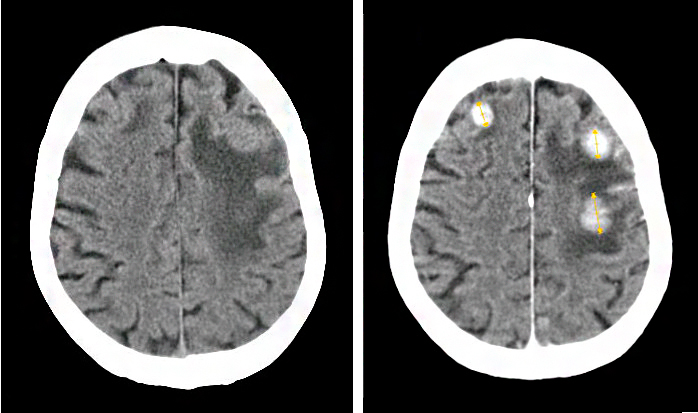

Для точной постановки диагноза прибегают к различным методам диагностирования:

- КТ. Этот метод помогает визуализировать даже бессимптомнее поражения у пациентов с экстракраниальными повреждениями (находящимися на поверхности органа);

- МРТ – наиболее информативный вид диагностики для исследования метастаз.